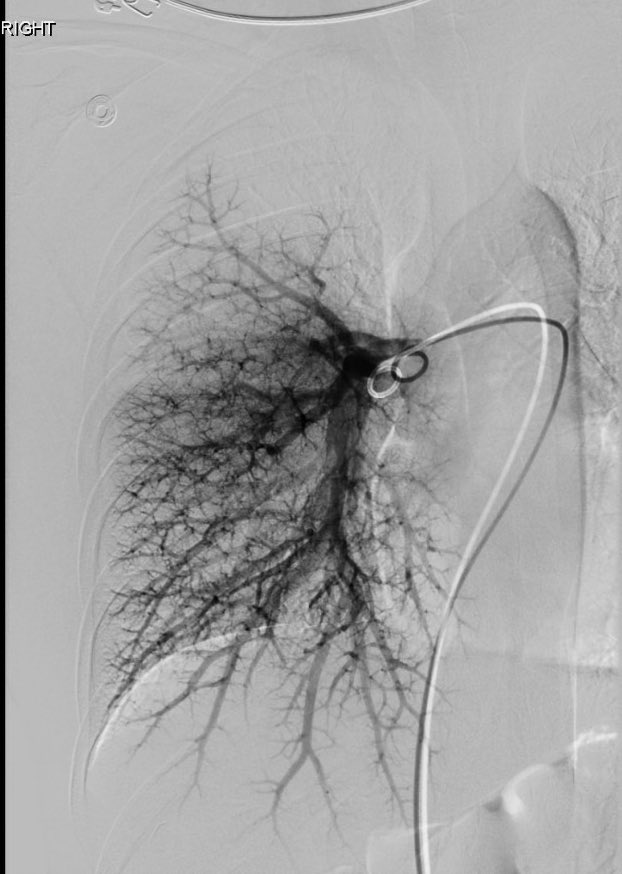

David Léon MD@IdCathThat·

Pulmonary AVM embolization in a patient with HHT using MVP and Ruby coils

David Léon MD tweet mediaDavid Léon MD tweet mediaDavid Léon MD tweet mediaDavid Léon MD tweet media

English